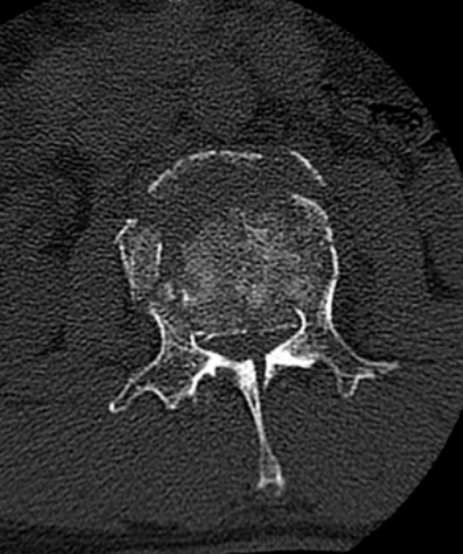

椎管压迫仅剩5毫米!骨科团队“精雕”碎骨,成功解除瘫痪危机

7月6日的傍晚,53岁的宋先生(化名)被工友匆匆送来急诊科,一场工作意外事故,让他的腰疼得直不起来,左腿发麻,行动能力完全丧失。

此次手术的成功实施,标志着对宋先生严重脊柱创伤的关键性胜利。绍兴袍江医院骨科团队在狭窄的空间内,精准完成了椎管减压、神经修复、脊柱复位与固定等一系列复杂操作,有效解除了脊髓压迫危机,重建了脊柱的力学结构。